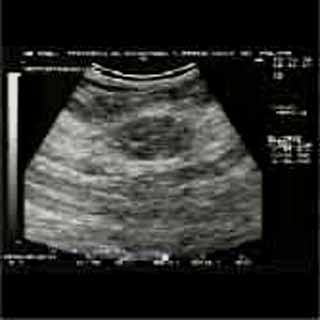

Η κλινικο-υπερηχογραφική διερεύνηση του μαστού είναι μία ακίνδυνη και πολύ αποτελεσματική μέθοδος εντόπισης εστιακών ευρημάτων.

Οι απεικονίσεις των περιστατικών που επιδεικνύονται παρακάτω, έγιναν με κυρτές κεφαλές 3,5 και 5 ΜΗΖ, προκειμένου να φανεί, ότι και με τον εξοπλισμό αυτό, που σιγά-σιγά διαθέτουν όλο και περισσότερα ιατρεία, είμαστε σε θέση να έχουμε ικανοποιητικά αποτελέσματα.